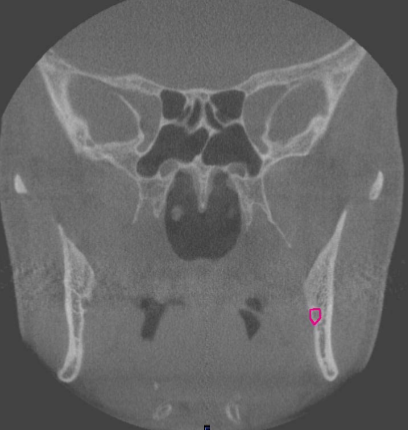

coronal

what plane

molar region

where is this slice located